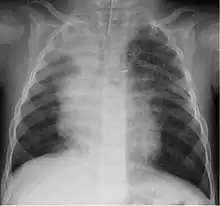

A study in Jordan found that 9% of 220 children hospitalized with lower respiratory tract infection were infected with bocavirus.[30] Of those infected the median age was 4 months. Coughing (100%), wheezing (82.7%) and fever (68.2%) were the most common clinical findings with bronchopneumonia (35%) and bronchiolitis (30%) being the most common ultimate diagnoses.

Although most cases are mild, severe respiratory disease has also been reported.[31]

Life-threatening infection caused by human bocavirus was described in previously healthy 20-months old prematurely born child.[32]